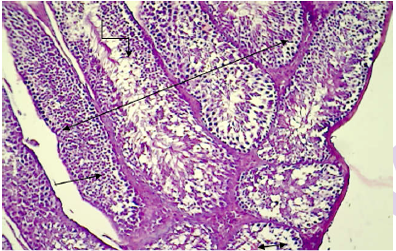

Histopathological section in testis of control animal reveals

Histopathological section in testis of control animal shows normal arrangement of the seminiferous epithelium.